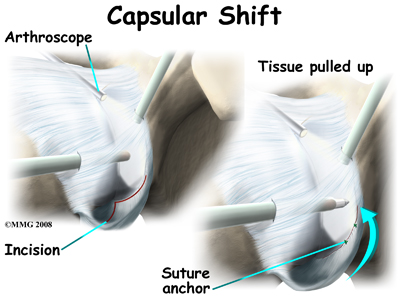

This procedure also can be performed using the arthroscope. The surgeon pulls the flap of tissue over the front of the capsule and connects it together. This is similar to when a tailor tucks loose fabric by overlapping and sewing the two parts together. Once the appropriate degree of tightness is achieved, the surgeon uses a combination of sutures and suture anchors to hold the joint capsule in this position until healing occurs.